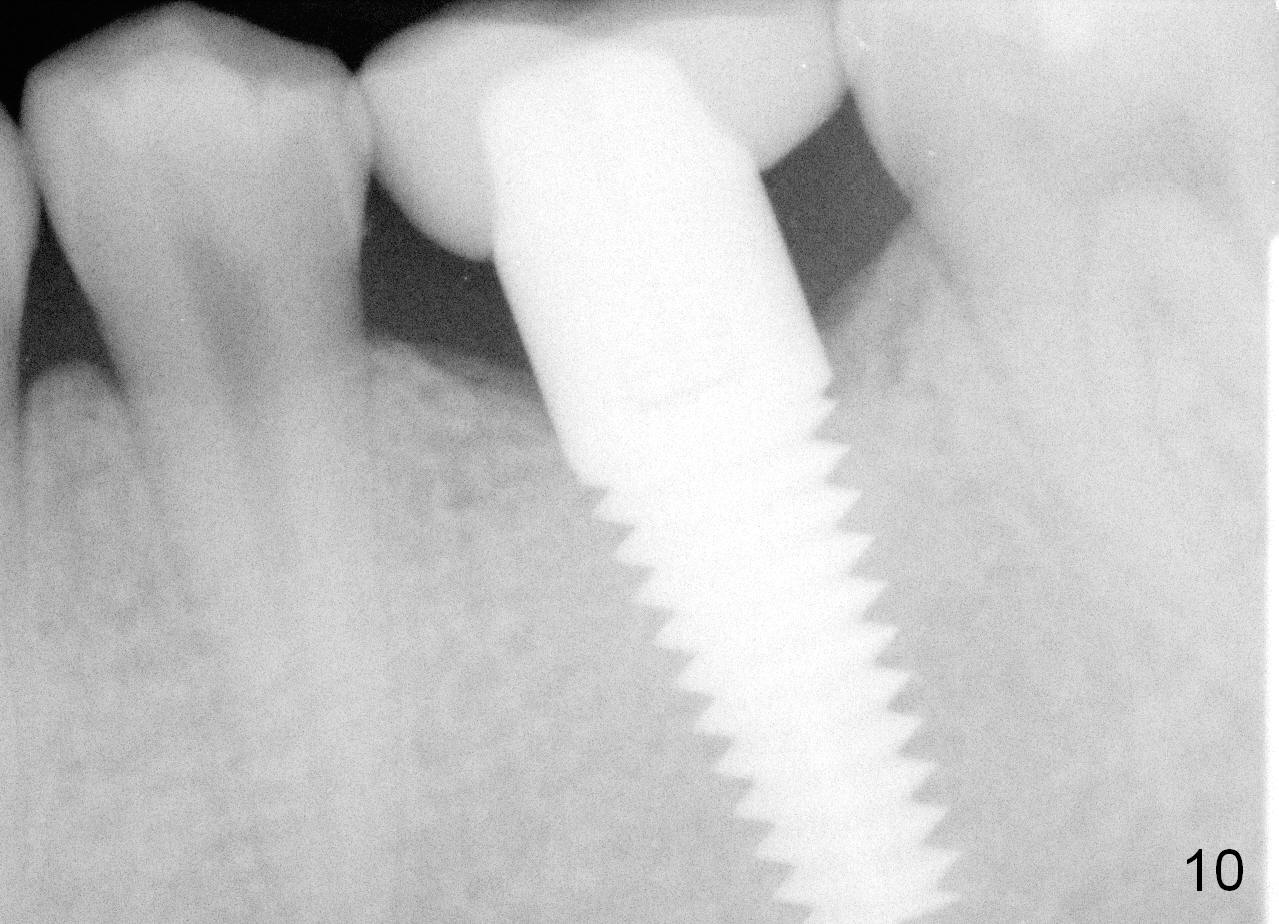

A 22-year-old man requested extraction of the tooth #19 (Fig.1).  X-ray was taken 3 and 8 months post extraction, respectively (Fig.2,3).  A 6x17 mm Tatum tapered implant was placed (Fig.4,5). A 5 mm (in diameter) 0 degree unipost (5 mm in height) was prepared 7 months after implant placement. Due to limited space, time was spent for extraoral and intraoral reduction of the abutment.

It appears that there is no bone resorption in height for patients at young age.  For their implant restoration, a shorter abutment (3 mm long, for example) should be fabricated to save precious clinical time.